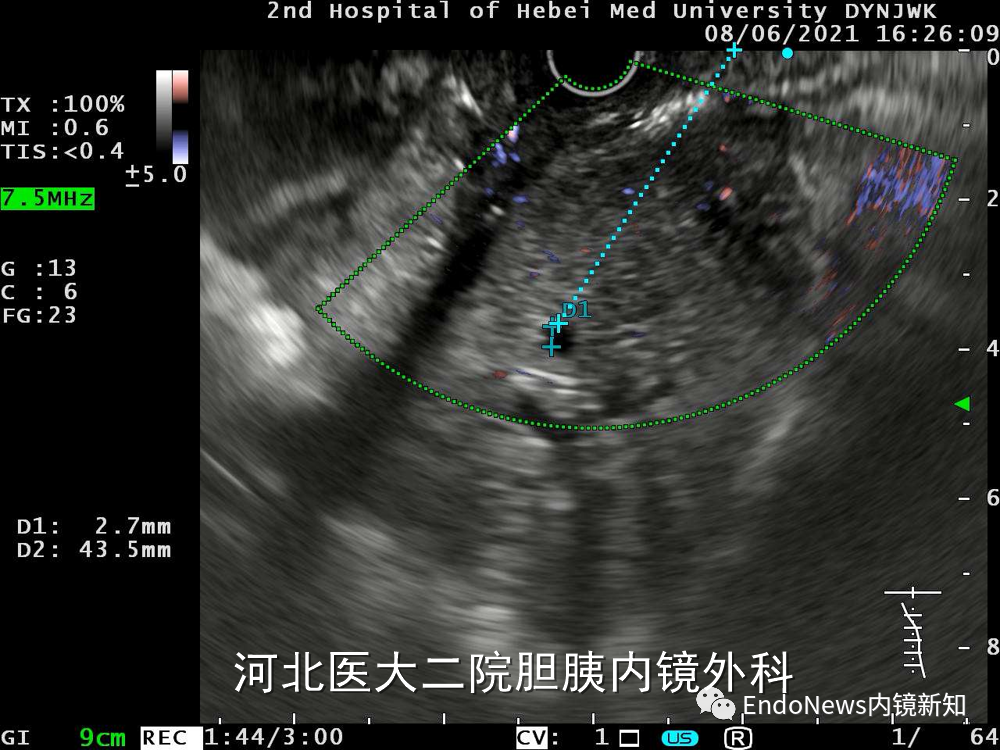

随后我们调整方法,试图从S3段穿刺,此位置胆管有2.7mm,但整个胆管扩张不是特别明显,并不是适合的位置,因此也放弃了S3段。